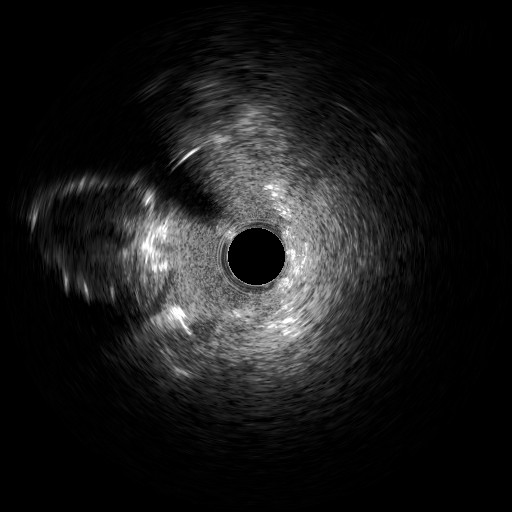

Four days later, the patient was admitted to the cardiology department because of exertional dyspnea. Because of the recent revascularization of the RCA, a new coronary angiography was performed. The angiography of the left system revealed no changes, but the RCA unveiled a nimble formation in the proximal part of the stented vessel (Figure 3, Video 3). An intravascular ultrasound was performed, which displayed the double-barrel configuration (Figures 4 and 5, Video 4) and the presence of a thrombus (Figures 6 and 7, Video 5). It was directly stented with an excellent angiographic result (Video 6). Two days postoperative, the patient was asymptomatic and discharged.